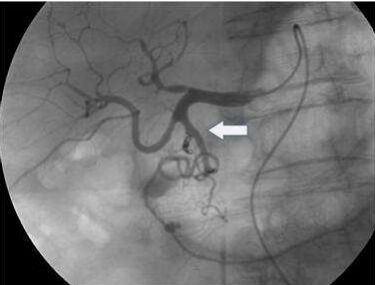

77.下圖中箭號所顯示為那一條血管出血?(A)左胃動脈(left gastric artery)(B)肝總動脈(common hepatic artery)(C)右肝動脈(right hepatic artery)(D)胃十二指腸動脈(gastroduedenal artery)

78.承上題附圖,發現出血後所執行之最適合治療應為: (A)血管成形術(PTA) (B)經動脈栓塞術(TAE) (C)經頸靜脈肝門脈系統靜脈引流術(TIPS) (D)血管支架置放(vascular stenting)